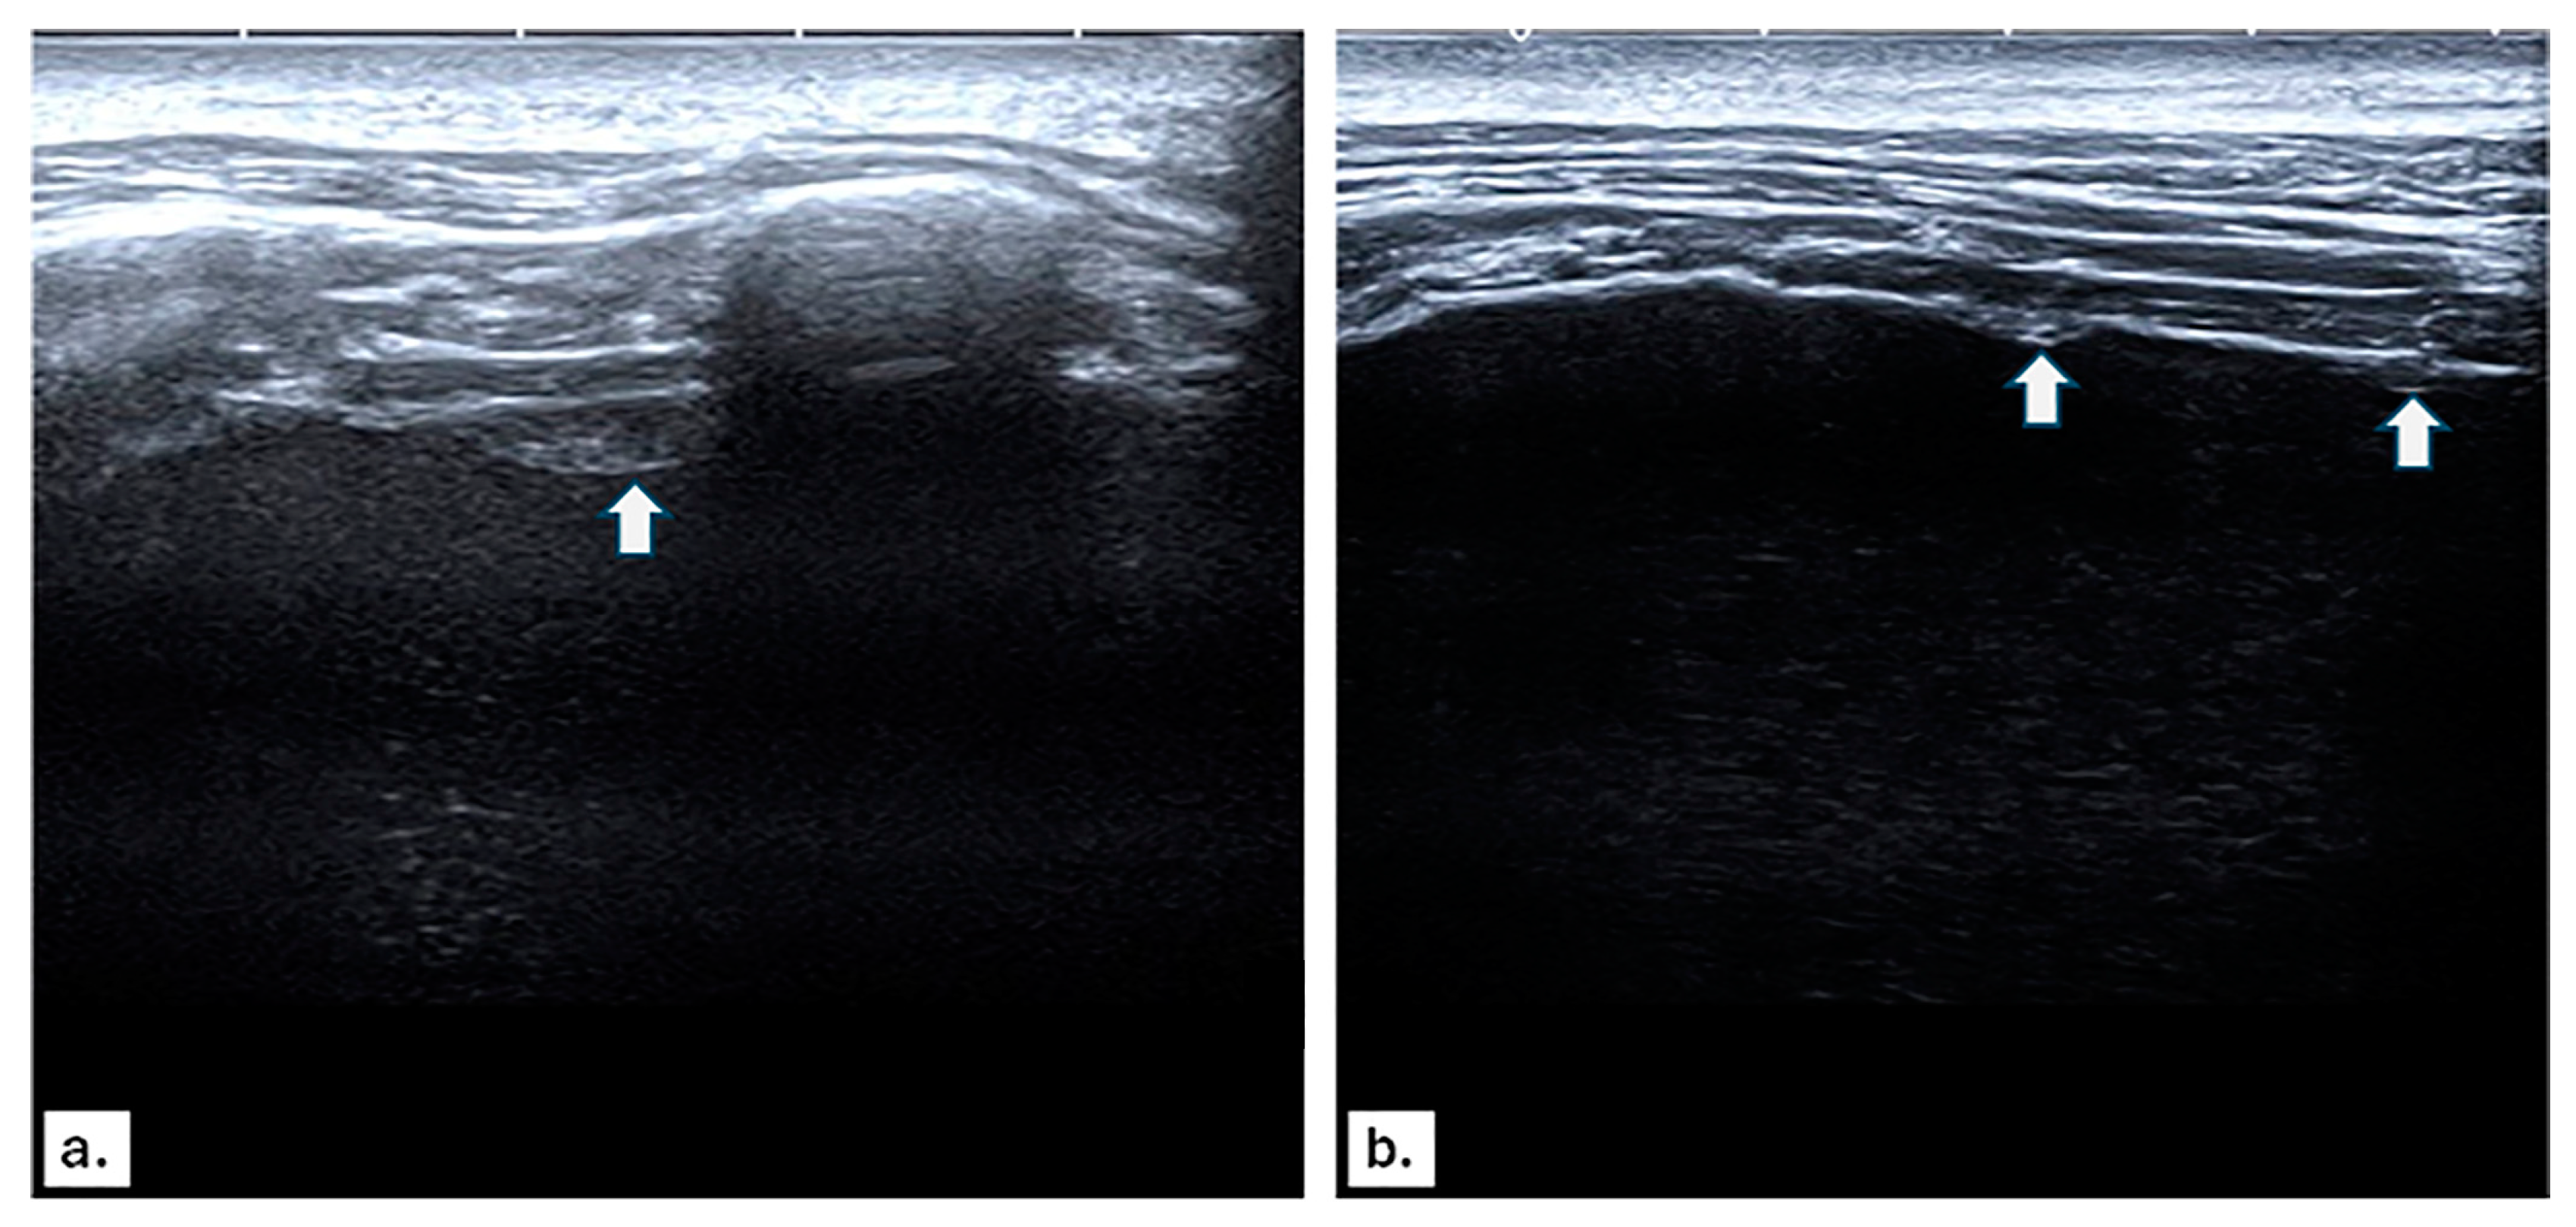

3.2. US and CT Findings in MPE

3.3. Imaging Findings in Benign Pleural Effusion